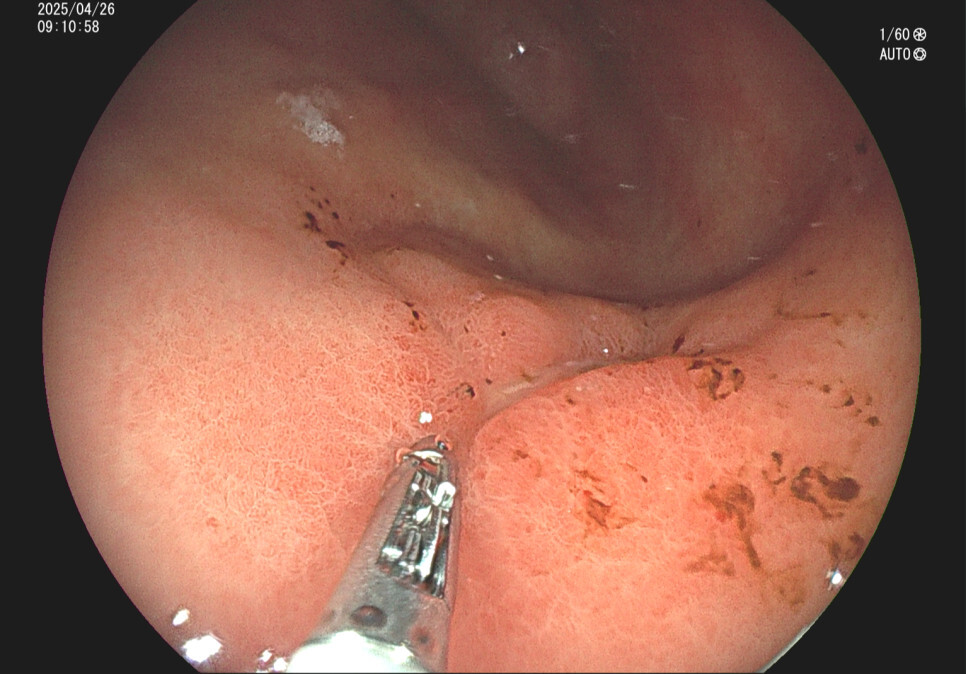

위궤양의 내시경 소견 증례입니다.

사례2. 36세 남성, 식후 속쓰림 증상으로 내원

과거 위내시경상 위궤양 의심 소견있었으나 치료 안하고 방치, 헬리코박터위염 확인됨.